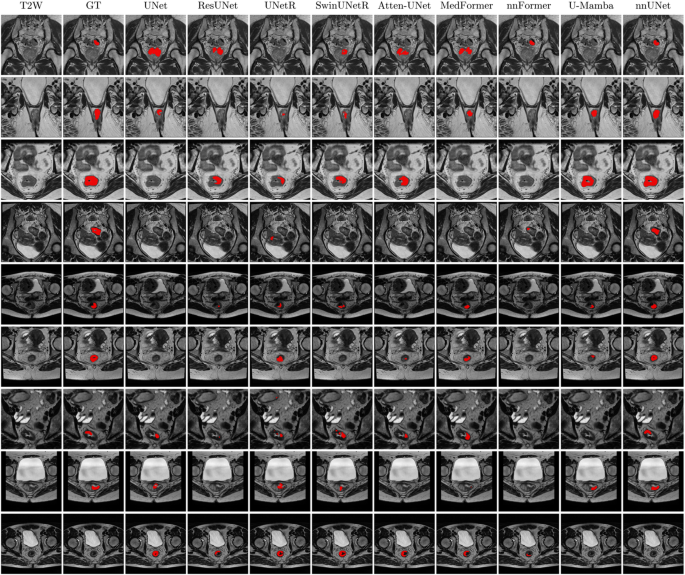

In the internal dataset (Training Cohort 1, 5-fold cross-validation), MedFormer delivered the best overall performance, with an average DSC (aDSC) of 66.3 and a median 95% HD (mHD) of 6.39 mm. U-mamba achieved the highest median DSC (mDSC), while ResUNet excelled in the average 95% HD (aHD), see Table S1. However, in the external testing data (num = 666, 9 centers), as is displayed in Table 3, S2, and Fig. 2a, nnUNet achieved the best results, with aDSC 62.8 and aHD 17.28 mm, significantly better than others. We observed that nnUNet consistently outperformed other models in the external test when the training cases was increased to 132 from a single center, see Tables S3, S4. Additionally, transformer-based networks including UNetR, SwinUNet, and nnFormer or the SSMs-inspired architecture like U-Mamba underperformed with respect to CNN-based architectures in external test. We also compared the size of trainable parameters and Floating Point Operations (FLOPs) for each model (Fig. 2b). In summary, nnUNet demonstrated the highest DSC despite having relatively few model parameters and a low number of FLOPs. From Fig. 3, nnUNet showed better prediction performance in identifying rectal tumors in the external test. nnUNet exhibited a significantly reduced false positive voxel classification in these displaying cases, especially in the last row of Fig. 3, which was a tumor-free slice.

The visualization of the segmentation performance of all nine DL models using T2WI. Each row is a different patient from a different center (external set). The columns from left to right are original T2WI, GT: ground truth, tumor prediction masks from UNet, ResUNet, UNetR, SwinUNetR, Atten-UNet, MedFormer, nnFormer, U-Mamba, and nnUNet.